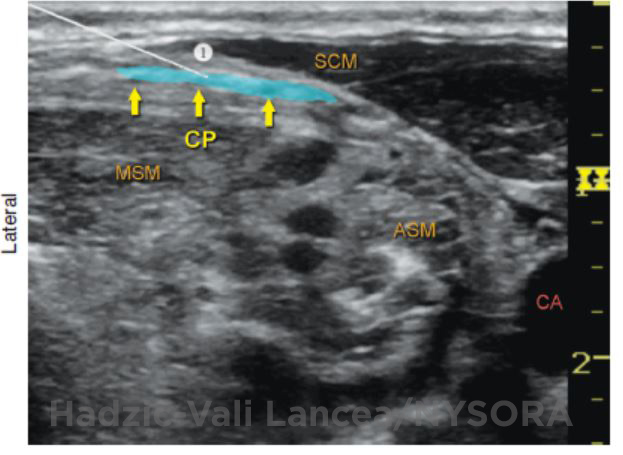

Ultrasound-Guided Femoral Nerve Block

Figure 1: Transducer position and needle insertion using an in-plane technique to block the femoral nerve at the femoral crease. Essentials  Indications: anterior thigh, femur, and knee surgery  Transducer position: transverse, close ... Full story